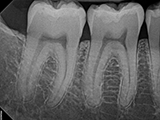

| X-Ray Example |

X-ray taken with the Dream Sensor |

Dental X-Ray Comparison

X-ray taken with the DentiMax sensorOpen Sensor

X-ray taken with the Caresream® sensorDexis